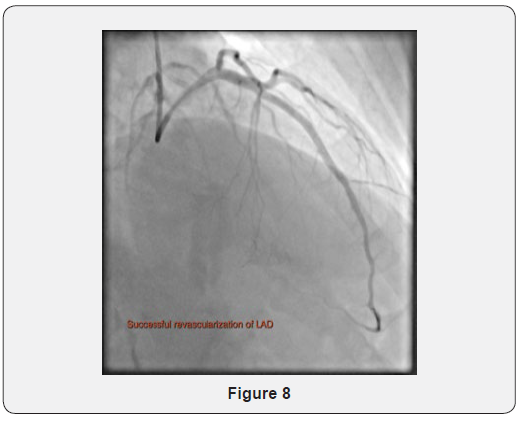

A larger 2x9mm Sprinter Legend NC (Medtronic) balloon was then passed and inflated to high pressures along the length of the CTO. Further pre-dilatation was then performed using a 2.5x30mm Sprinter Legend NC (Medtronic) balloon along the length of the CTO to high pressures. An area of significant distal LAD became more apparent on anterograde angiography and this was treated using a 2.5x10mm Sequent Please Neo drug-eluting balloon (B Braun) and a 2.25x30mm Sequent Please Neo drugeluting balloon (B Braun) with 50 second inflations. The mid LAD was then treated using overlapping 3x23mm and 2.5x33mm Xience Sierra evorlimus-eluting stents (Abbott) to high pressure. The stent overlap was post-dilated using the 3x23mm Xience Sierra stent balloon to high pressure. Anterograde coronary angiography post PCI demonstrated an excellent angiographic result (Figure 8).